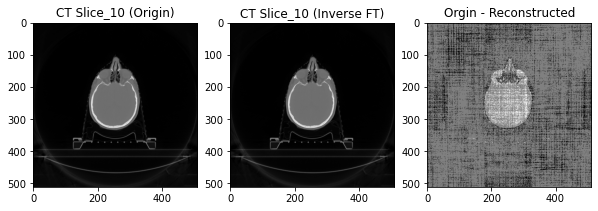

plt.figure(figsize=(10, 10))plt.subplot(131)plt.title('CT Slice_10 (Origin)')plt.imshow(imgs_ct[10], cmap='gray')plt.subplot(132)plt.title('CT Slice_10 (Inverse FT)')plt.imshow(ct_ift, cmap='gray') # we apply a logarithmic transformation here to better display the dynamic range of the magnitudeplt.subplot(133)plt.title('Orgin - Reconstructed')plt.imshow(np.round(imgs_ct[10] - ct_ift), cmap='gray')plt.show()

直观上可以看到,重新得到的图像与原图之间有一定差别,但通过np.max(imgs_ct[9] - ct_ift)得到结果为1,这表示像素点间的差别很小(最大仅为1),所以可以认为重新得到的图像基本等于原图。